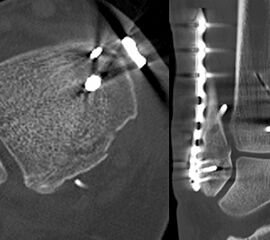

Gardner et al. konnten beispielsweise zeigen, dass die offene anatomische Reposition der Tibiahinterkante der Stabilisierung mittels Stellschraube überlegen war und gleichzeitig mit einer geringeren Rate an postoperativen Fehlstellungen der Fibula in der CT-Kontrolle einherging 2728. Aus Sicht der Autoren ist prinzipiell die Stabilisierung über eine direkte Reposition indiziert, wenn die Größe des Fragmentes dies erlaubt. Bei gleichzeitigem Vorliegen einer Fraktur des lateralen und/oder medialen Malleolus sollte zunächst die Versorgung der des Tibiahinterkantenfragments erfolgen. Dies erlaubt die radiologische Kontrolle der Reposition und Osteosynthese-Lage, welche durch eine zuvor aufgebrachte Fibula-Platte häufig erschwert ist 29. Dafür werden die Patienten in Seitenlage gelagert. Dies erlaubt die direkte Versorgung der posterioren Malleolusfraktur über einen posterolateralen Zugang 30. Das sehr kräftige Periost wird im Frakturverlauf inzidiert und aus den Frakturspalt entfernt, so kann eine anatomische Reposition erfolgen. Entsprechend der Fragmentgröße erfolgt entweder die Versorgung mittels Drittelrohrplatte in Antiglide-Technik oder eine Zugschraubenosteosynthese. Die Versorgung der Fibula-Fraktur gelingt über den gleichen Zugang. Zur Versorgung des medialen Malleolus wird der Patient auf den Rücken umgelagert. Dies kann bei entsprechender Vorbereitung ohne erneutes steriles Abdecken erfolgen. Durch dieses Vorgehen konnte im eigenen Kollektiv die Notwendigkeit einer Stabilisierung der Syndesmose mit Stellschraube/Tight Rope deutlich reduziert werden.

Liegt eine Syndesmosen-Insuffizienz vor (Abbildung 18), so erfolgt nach der Osteosynthese aller Frakturen im ersten Schritt die Reposition der Fibula in die Incisura fibularis der Tibia mittels Repositionszange. Danach sollte geprüft werden, ob die Dorsalextension im OSG noch uneingeschränkt möglich ist. Falls vorhanden, ist es hilfreich die korrekte Reposition mittels intraoperativen CT zu kontrollieren. Die Durchführung eines intraoperativen 3D Scans konnte nach zufriedenstellenden Ergebnissen in der konventionellen 2D Bildgebung bereits intraoperativ in 20-40% ein korrekturbedürftiges Ergebnis zeigen 3132. Anschließend erfolgt das Einbringen einer Stellschraube oder eines Tight Ropes (Abbildung 19). Dabei sollte darauf geachtet werden, dass die Bohrung knapp proximal des distalen Tibio-Fibular-Gelenkes angelegt wird. Die Bohrung sollte in 30° von posterior nach anterior und parallel zur Gelenklinie des OSG gerichtet sein. Beim Einbringen der Schraube ist darauf zu achten, die Fibula nicht an die Tibia zu komprimieren. Postoperativ empfehlen wir die Durchführung einer CT-Untersuchung des verletzten und des unverletzten Sprunggelenkes. Nur so ist aus unserer Sicht die Reposition der Fibula sicher zu beurteilen.